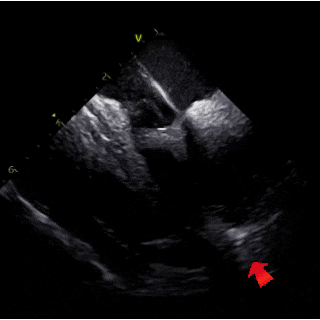

ICE下可见明显长隧道PFO

ICE下测量膨出瘤基底24mm

选伞考量:术前RLS为大量,ICE下可见明显长隧道PFO,并且合并基底24mm的房间隔膨出瘤,拟选择对称型封堵器BDPFO-I 3434,16F可降解封堵器介入输送系统。